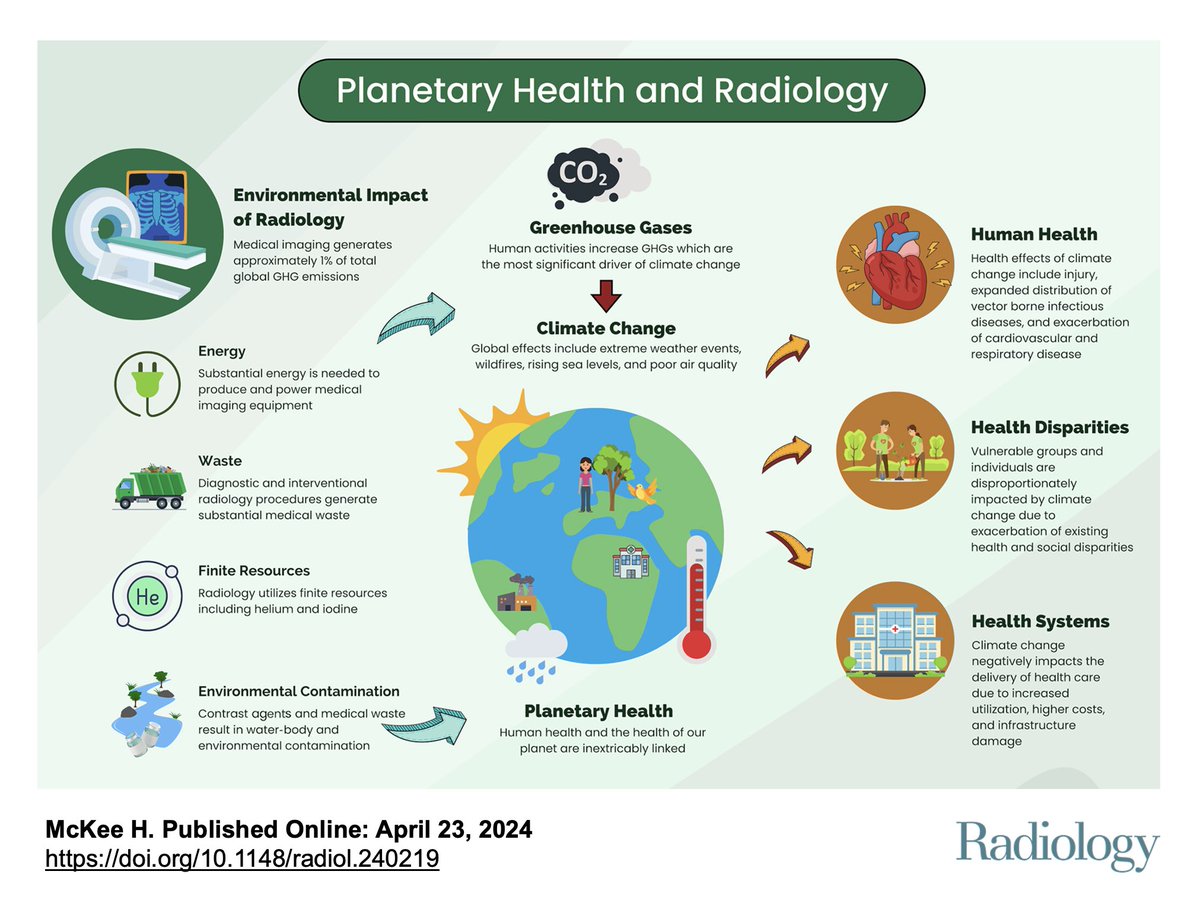

Excited to share our Radiology review on #PlanetaryHealth and #Radiology 🩻🌎🌿#EarthDay pubs.rsna.org/doi/10.1148/ra… Very grateful to work with this wonderful team 😊Hayley McKee Maura Brown 🇨🇦 Helen Kim, MD Flo Doo, MD HayleyPanet Andrea Rockall Reed Omary, MD, MS University Medical Imaging Toronto (UMIT) Radiologists for a Sustainable Future (R4SF)